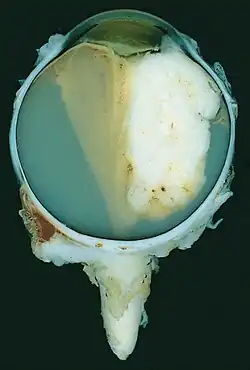

| A pathology specimen of a retinoblastoma tumor from an enucleated eye of a 3-year-old female | |

Morphology

Gross and microscopic appearances of retinoblastoma are identical in both hereditary and sporadic types. Macroscopically, viable tumor cells are found near blood vessels, while zones of necrosis are found in relatively avascular areas. Microscopically, both undifferentiated and differentiated elements may be present. Undifferentiated elements appear as collections of small, round cells with hyperchromatic nuclei; differentiated elements include Flexner-Wintersteiner rosettes, Homer Wright rosettes,[31] and fleurettes from photoreceptor differentiation.[32]